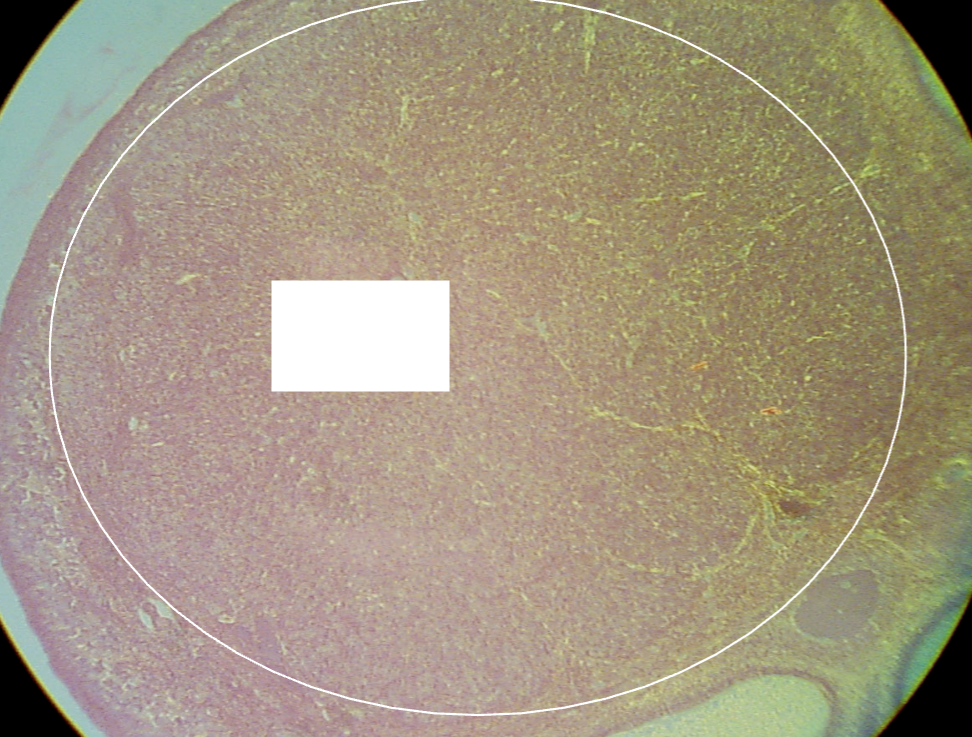

What is the structure being shown in this image?

*Hint: The ovulated follicle is transformed rapidly into this new, highly vascularized, glandular structure.

Corpus luteum

*Hint: With time, a hyaline intercellular material accumulates, and the former corpus luteum assumes the appearance of an irregular white, hyaline scar.

Corpus albicans